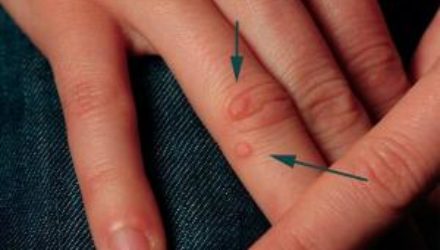

Простой способ помогает избавиться от бородавок

Медицинский эксперт из Мюнхена Сабрина Никель поделилась очень простым способом избавиться от бородавок – с помощью яблочного уксуса. Эксперт поясняет:...